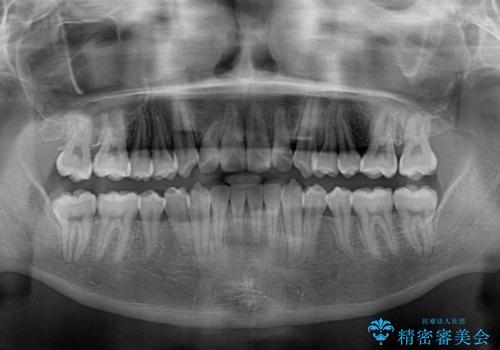

全顎的なクロスバイト 補助装置を用いてワイヤー矯正

- 2年1ヶ月

前歯のクロスバイトや八重歯の他に、左右最後臼歯のシザーズバイト(鋏状咬合)が認められました。

シザーズバイト改善のために補助装置を使用しながら、ワイヤー装置にて全体の歯列を整えることとしました。

シザーズバイトは強く咬合する奥歯を移動させるため、多くの場合においてワイヤー矯正の装置のみでは改善が困難となります。

奥歯の咬み合わせ改善は治療初期からしっかりとアプローチする必要があるため、補助装置を積極的に利用します。